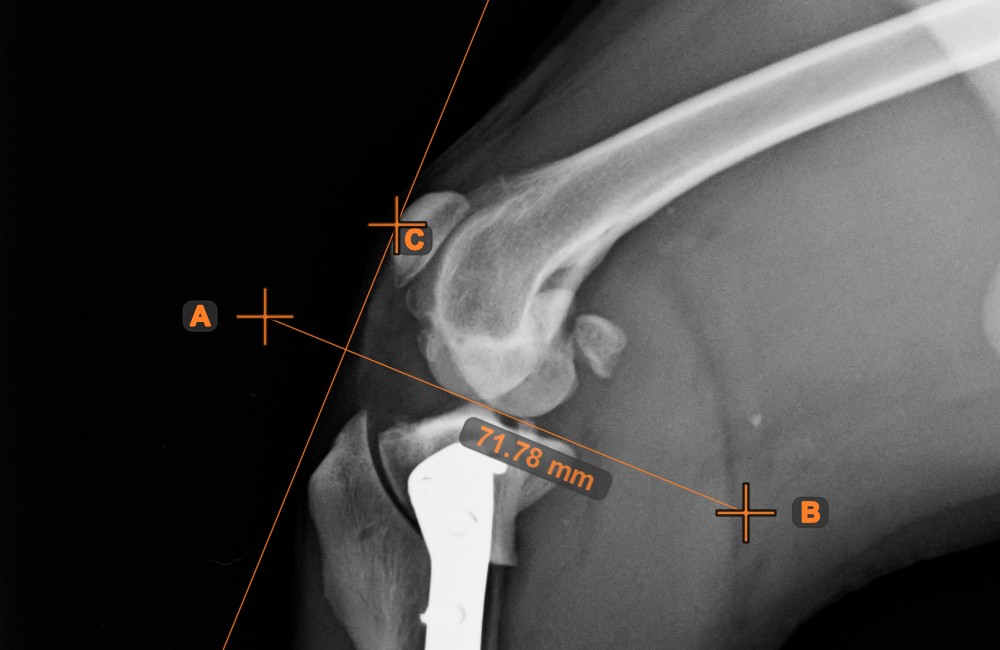

Erstellen Sie eine Linienmessung, um den Abstand zwischen zwei Punkten mit hoher Genauigkeit zu berechnen.

Wählen Sie das Werkzeug Linienmessung aus und weisen Sie es einer der verfügbaren Maustasten zu. Setzen Sie die Start- und Endpunkte in der Szene oder wählen Sie sie aus bereits vorhandenen Punkten im Bild aus. Der Abstand zwischen den beiden Punkten wird automatisch anhand der Standardkalibrierdaten oder der durch die Längenkalibrierung-Messung neu kalibrierten Daten berechnet.

Ändern Sie den Start- und Endpunkt mit dem Werkzeug Objekt auswählen/verschieben. Der Abstand zwischen den beiden Punkten wird automatisch neu berechnet.

Winkel zwischen Linien¶

Berechnen Sie den Winkel zwischen zwei unabhängigen oder sich schneidenden Linien mit dem Werkzeug Winkel zwischen Linien.

Wählen Sie das Werkzeug aus der linken Symbolleiste aus und weisen Sie es einer der verfügbaren Maustasten zu. Beginnen Sie, indem Sie die erste Linie aus den bereits in der Szene gezeichneten Linien auswählen oder Start- und Endpunkt setzen, um die Linie zu erstellen. Wiederholen Sie die gleichen Schritte für die zweite Linie der Messung. Der Winkel zwischen den beiden Linien wird automatisch berechnet.

Ändern Sie die Start- und Endpunkte beider Linien mit dem Werkzeug Objekt auswählen/verschieben. Der Winkel zwischen den beiden Linien wird automatisch neu berechnet.